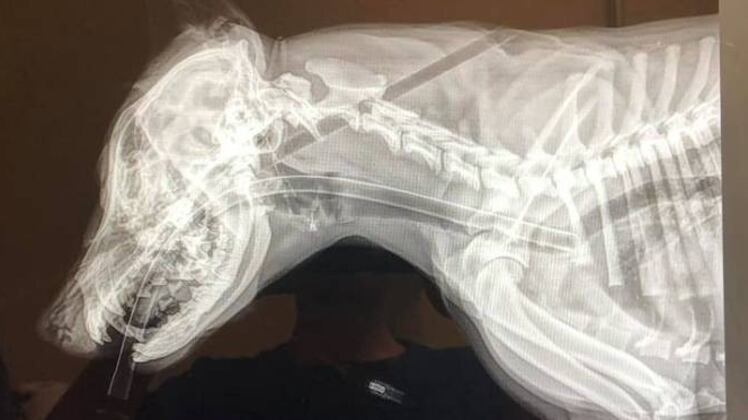

Las imágenes son verdaderamente impactantes y terribles. Una perrita de sólo 5 meses con una flecha clavada en la cabeza y que sale en el lomo.

De inmediato la llevaron a un centro de rehabilitación animal y ahí procedieron a salvarle la vida. Ahí la estabilizaron, le quitaron la flecha y afortunadamente sus signos vitales estaban bastante bien.

Acá puedes ver las imágenes, pero te advertimos, son muy fuertes.